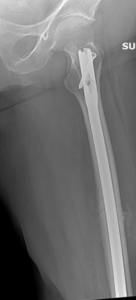

The thigh bone is a mostly tubular structure throughout its length. The tubular portion is termed the femoral shaft. Fractures of the shaft of the femur most commonly occur from a high energy mechanism in younger people, whereas they can more commonly occur from a low energy injury in elderly people with poor bone quality. Treatment often consists of a rod that is placed down the central portion of the femur (also known as the femoral canal), and this rod is secured to the bone at both ends with screws. Typically, this rod will provide enough support to allow some weight bearing even before the bone has healed (the orthopaedic surgeon will determine weight bearing status on a case by case basis, however).

Femoral shaft fractures can also occur in individuals who have had previous orthopaedic surgery, such as hip replacement. In this instance, there is already a device occupying the femoral canal (the hip stem). Plates and screws are one possible treatment in this situation where a rod cannot be placed.